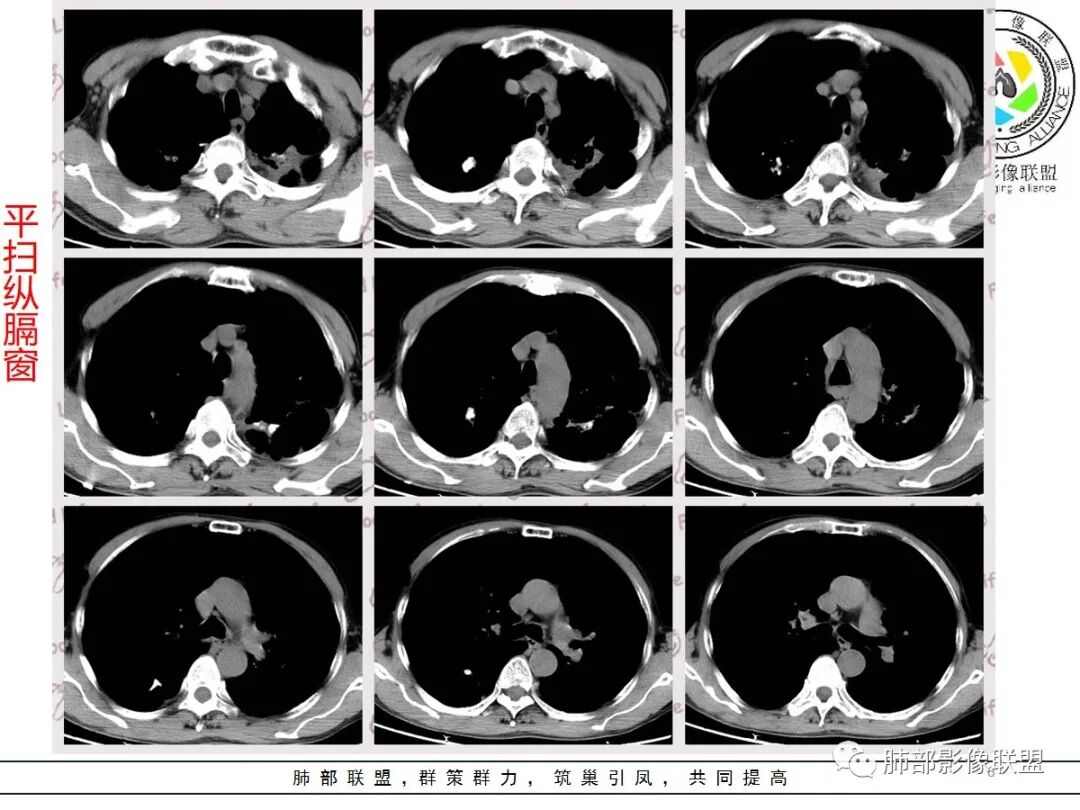

老年男性,肺气肿背景,结核病史。右肺下叶病灶,分叶不明显,局部可疑栽赃,毛刺略呈毛刷感,远端阻塞性肺炎改变,轻微强化,走行血管僵硬,湖泊样坏死,考虑鳞癌。左肺病灶边缘有分叶、毛刺及胸膜牵拉的恶性征象,也有平直收缩的良性征象,可疑卫星灶,这类良恶征象都有判断比较纠结,常规思路:炎性放前边,腺癌待排。

临床病史很长,背痛9年可能与左侧胸膜炎有关。两上肺陈旧性结核伴肺气肿没有问题。左下肺病灶,分叶毛刺、胸膜凹陷、指状凸起,增强轻度强化,腺癌问题不大。右侧附加题有些困难,病灶内血管显影,不像结核的表现,先把结核否掉?鳞癌和慢性脓肿的鉴别:支持良性的征像,低密度区内也有细小血管影,不像鳞癌坏死?与胸膜关系整体还是比较和谐,边缘还算光整,毛刺都在远端,不支持慢性脓肿的的地方,周围支气管管壁都很干净。恶性征像,与支气管的关系图片给的不够。坏死边缘不光整,有些浅分叶。总体,我觉得坏死区血管的存在更有价值,验证一下,右侧首先考虑慢性脓肿。

患者老年男性,因咳嗽 咳痰 背痛就诊。既往有喉及肺结核病史。胸部CT:左下肺实性病灶,边缘可见短硬毛刺,分叶,胸膜牵拉,增强可见强化,考虑肺腺癌。

右下肺实性病灶,进入病灶支气管阻塞,支气管壁增厚,病灶内可见坏死,内壁凸凹不平,增强可见病灶强化,考虑恶性病变,鳞癌?

老年男性,肺气肿背景,左肺下叶结节,深分叶,毛刺,胸膜牵拉,内部可见坏死,坏死边界不清,不均匀强化。右肺下叶大肿块,边缘有毛刺,多发小灶性坏死,胸膜下有侵犯,考虑恶性,左肺下叶腺癌,右肺下叶低分化鳞癌。

男,64岁,咳嗽咳痰,气喘10余年,右肺下叶软组织密度肿块影,边界清晰,边缘见细短毛刺及分叶,轻度胸膜粘连,病灶内密度不均,增强扫描看见坏死区,病灶边缘明显强化,考虑鳞癌可能。左肺下叶病灶深分叶、毛刺、胸膜牵拉,考虑腺癌可能,除外转移性病变。

双肺陈旧性肺结核,肺气肿背景。右肺下叶肿块,边缘毛糙,内部可见大片低密度坏死,环形强化,坏死边界清楚,考虑鳞癌。左肺下叶结节,边缘可见毛刺,深分叶,有收缩,有膨隆,胸膜牵拉,考虑腺癌。

1.左侧分叶深一些

2.右侧糊墙

左侧胸膜凹陷

3.左侧支气管显示欠佳,似乎在门口堵塞

右侧支气管门口堵塞,有推移迹象

4.右侧坏死明显,内部囊变坏死边缘部分清楚、部分不清

左侧坏死不明显

左肺分叶毛刺,支持腺癌,右肺肿块湖泊样坏死,边缘毛糙,壁厚不均匀,肺气肿背景,支持鳞癌

主要征象:病灶分叶不明显、较光整,局部胸膜栽赃,支气管门口堵塞,有推移迹象;增强后坏死明显,内部囊变坏死边缘部分清楚、部分不清楚,病灶内可见血管,局部稍毛糙,实性部分强化较明显,总体考虑恶性病变。一部分征象指向鳞癌(支气管截断、坏死较多,病灶内血管破坏),但又有肉瘤的一些特点(病灶较大,缺乏分叶,坏死边界清晰),要考虑到肉瘤样癌。